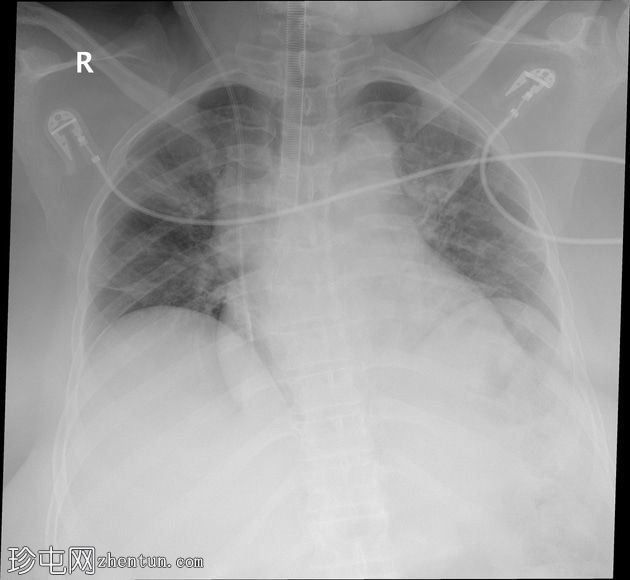

患者接受开颅手术后,现进行术后胸部X光检查,以评估导管和气管的情况。

移动式X光片显示患者吸气用力减弱,伴有预期的门充血、支气管血管纹理增多、误吸改变,以及麻醉后肺不张。心脏和纵隔轮廓正常,但图像放大。

装甲气管插管 (ETT) 位置过深,需要回缩。

右侧颈内静脉通路中心静脉导管尖端位置过深,需要回缩。

存在重叠的心电图导联。

患者接受了后颅窝减压术,术后要求进行胸部X光检查,之后患者才可俯卧位。